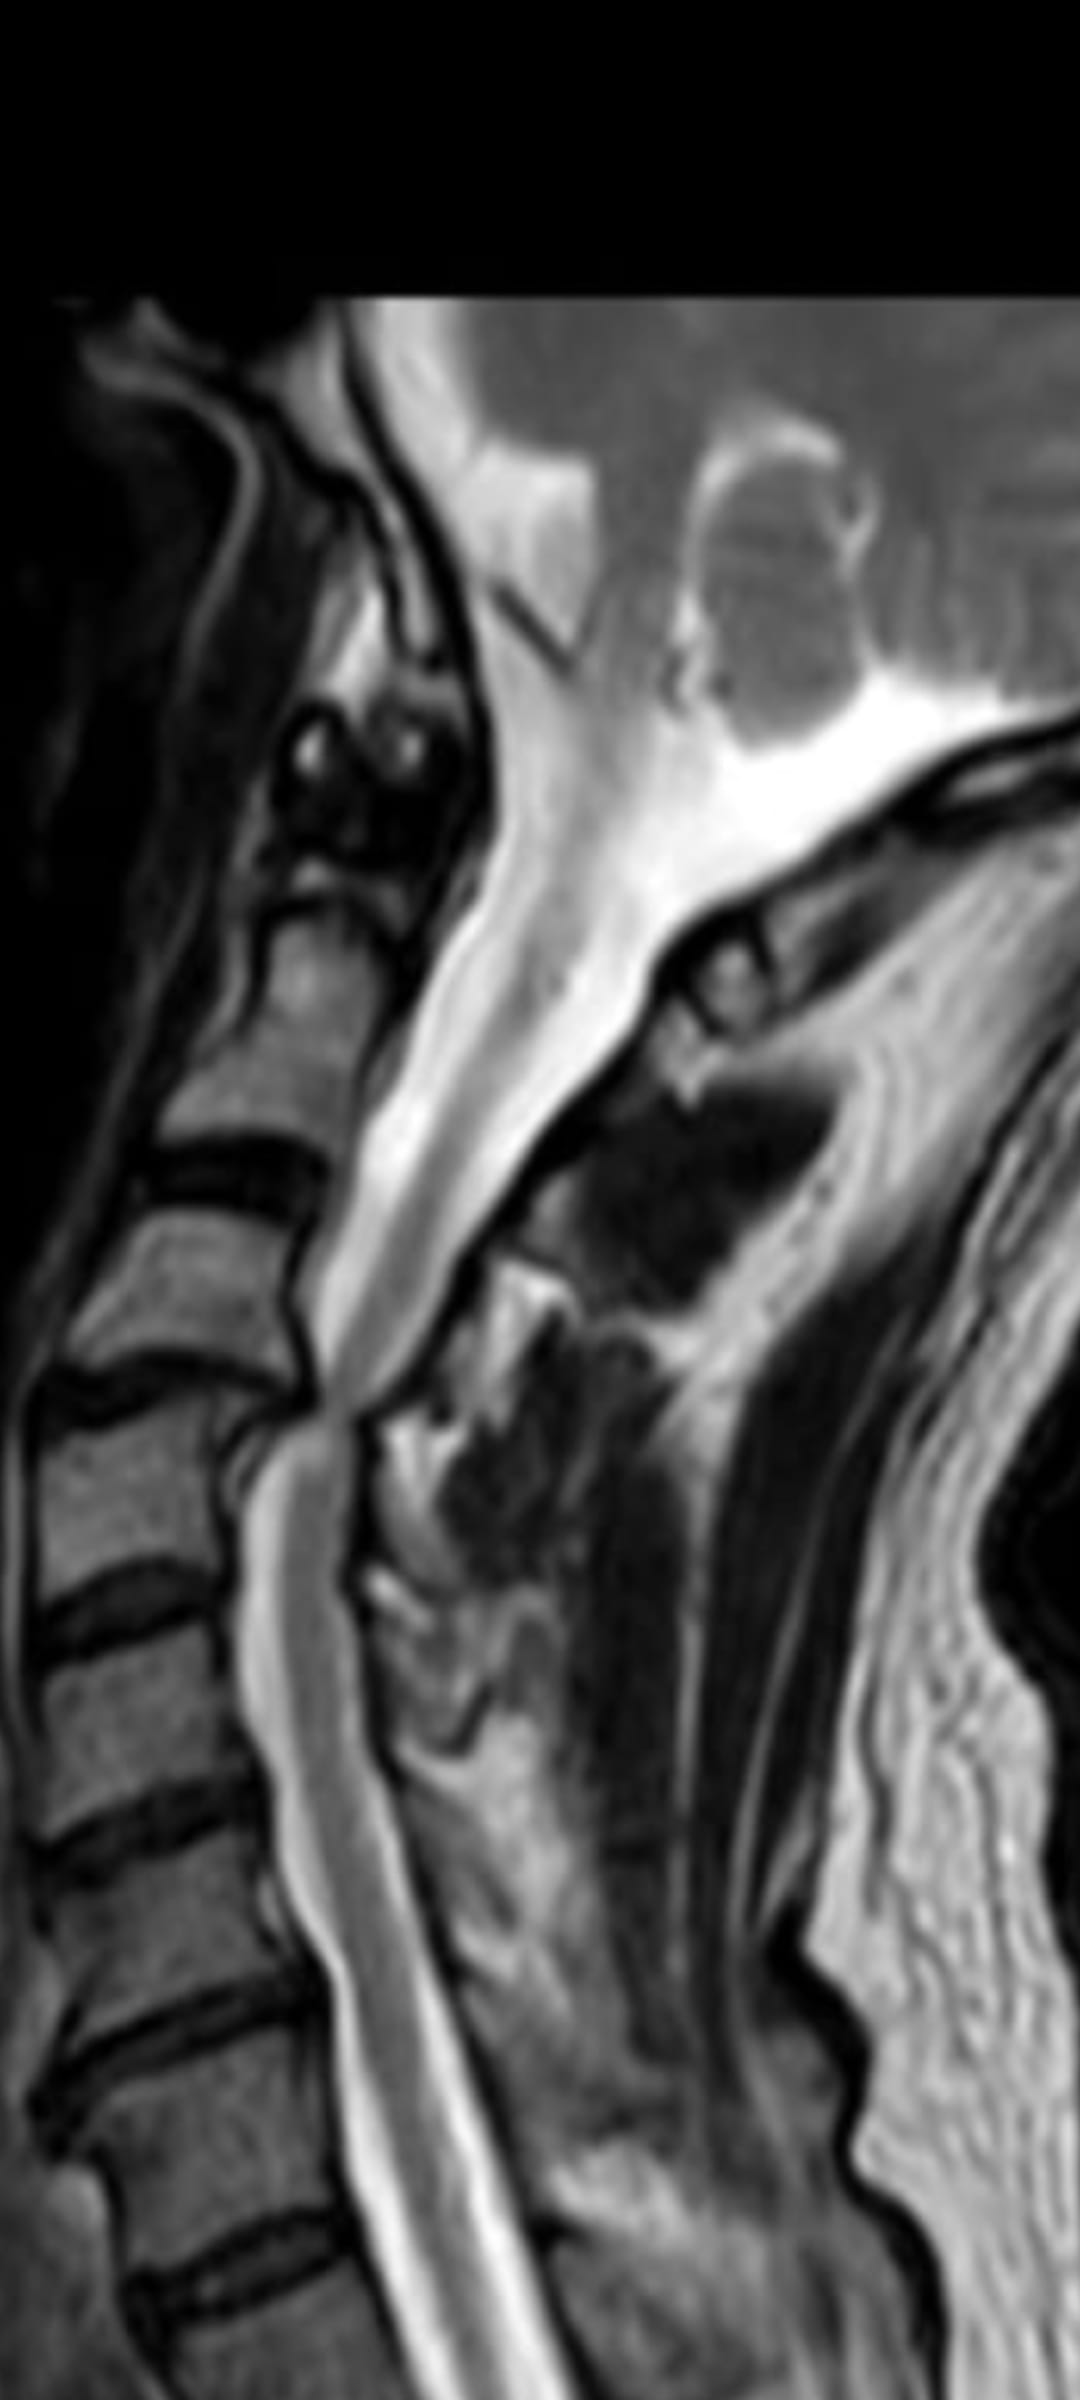

Bonjour je viens de me faire opérer hier d'une décompression de la moelle épinière à l'étage C3 C4 avec pose d'une cale arthrodèse. Cette compression provient d'une coup de lapin que j'ai eu hier maintenant plus de 30 ans. Je vous joins une petite photo de l'IRM montrant cette compression. J'avais des symptômes neurologiques qui devenait très inquiétant avec l'arthrose. Si au niveau des douleurs para cervicale et musculaire cela a l'air d'aller mieux j'ai toujours la sensation d'endormissement les pieds et de la main gauche. Pensez-vous que ces symptômes neurologiques se résorberont au fil du temps . merci de vos réponses